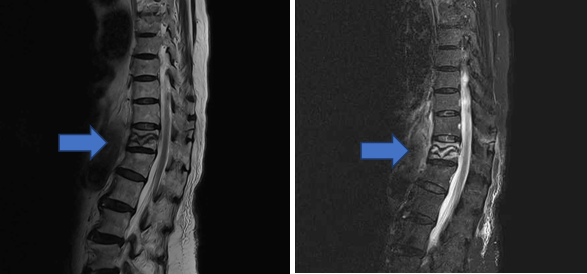

核磁共振(MRI):對於脊椎壓迫性骨折,MRI是最精確且最敏感的診斷工具,可以偵測骨頭內的訊後是否有水腫或出血,以區分新發生或陳舊骨折。也可用於診斷脊椎腫瘤。另外也是唯一可以看清楚軟組織,如椎間盤、黃韌帶及神經的影像檢查。缺點是檢查時間較久,排程等待時間也較久。(圖四)

(圖四)